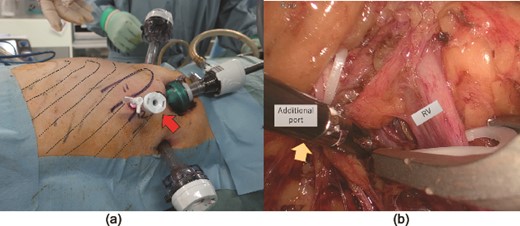

The patient was placed in the left lateral decubitus position. The retroperitoneal space was created using a PDB balloon dissector (Covidien Ltd., Mansfield, MA, USA). The ports were placed as shown in Fig. 2a. Although the renal vessels could be exposed, vascular control is difficult. Forceps could not reach the suprahilar area via the lateral port because the iliac crest interfered with forceps movement (Fig. 2b). Therefore, according to the preoperative plan, a 5 mm port was added at the intercostal site, as indicated in Fig. 3a. The trocar accessed the retroperitoneal space directly without injuring the pleura or diaphragm. The additional port secured the manual placement of the suprahilar area and ensured safe vascular control. The port also secured the handling of the superior aspect of the kidney and the successful completion of laparoscopic surgery (Fig. 3b). The lower ureter and bladder cuff were dissected, and en bloc specimens were retrieved via a Gibson incision.

Port position at the beginning of retroperitoneal laparoscopic surgery (a).

indicates the port for the camera, ◯ refers to the 12 mm left and right ports for manipulation, and □ is the 5 mm port site for the assistant. (b, c) Manipulation of renal vessels was complex because the forceps could not reach the suprahilar area through the lateral ports (☆). Dotted lines indicate the ribs. RA: renal artery.